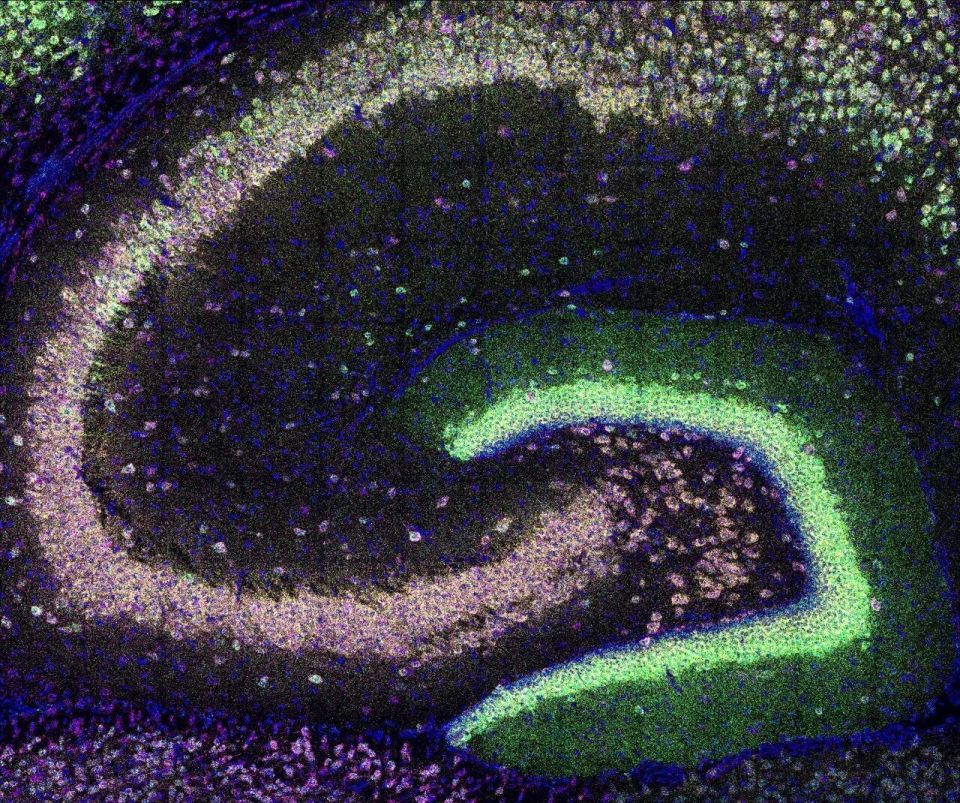

这张由多张高倍率图像拼接而成的大型复合图显示了幼鼠海马神经毡中定位的四种 mRNA。神经毡是位于细胞体之外的一层致密突触连接网络。使用 HiPlex RNAscope 原位杂交法对 mRNA 进行标记,以检测 Adcy1(绿色)、Aco2(品红色)、Psd(青色)和 Dlg4(黄色),并用 DAPI(蓝色)对细胞核进行复染。该技术用于说明这些 mRNA 由于其含量丰富而自然地紧密排列。Credit: Shannon Farris/Virginia Tech

研究团队利用高通量单分子荧光原位杂交(HiPlex smFISH)技术,在小鼠海马组织中对15种关键的mRNA分子进行了高精度的空间成像。通过测量66种不同mRNA组合的空间分布,研究人员发现,mRNA在神经元突起中的聚集并非源自复杂的“打包”机制,而是遵循基于丰度的随机相互作用。换言之,细胞产生的某种mRNA越多,它们在空间上与其他mRNA重叠的概率就越高。这一发现挑战了mRNA以特定功能组合进行运输的传统观点,表明系统具有更高的灵活性。该研究不仅阐明了支持突触可塑性的基础生物学机制,也为理解脆性X综合征(Fragile X syndrome)等神经发育障碍中分子信号传递的故障提供了新的视角。研究发表在 eNeuro 上。